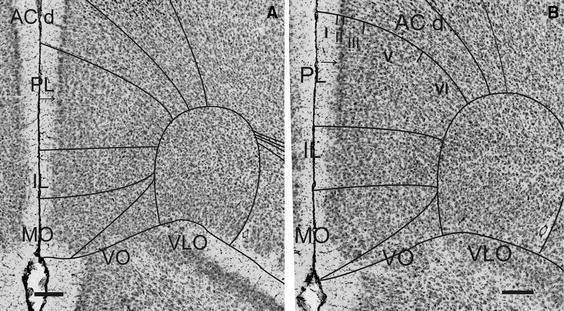

Cytoarchitectonic and chemoarchitectonic characterization of the prefrontal cortical areas in the mouse.

This study describes cytoarchitectonic criteria to define the prefrontal cortical areas in the mouse brain (C57BL/6 strain). Currently, well-illustrated mouse brain stereotaxic atlases are available, which, however, do not provide a description of the distinctive cytoarchitectonic characteristics of individual prefrontal areas. Such a description is of importance for stereological, neuronal tracing, and physiological, molecular and neuroimaging studies in which a precise parcellation of the prefrontal cortex (PFC) is required. The present study describes and illustrates: the medial prefrontal areas, i.e., the infralimbic, prelimbic, dorsal and ventral anterior cingulate and Fr2 area; areas of the lateral PFC, i.e., the dorsal agranular insular cortical areas and areas of the ventral PFC, i.e., the lateral, ventrolateral, ventral and medial orbital areas. Each cytoarchitectonically defined boundary is corroborated by one or more chemoarchitectonic stainings, i.e., acetylcholine esterase, SMI32, SMI311, dopamine, parvalbumin, calbindin and myelin staining.